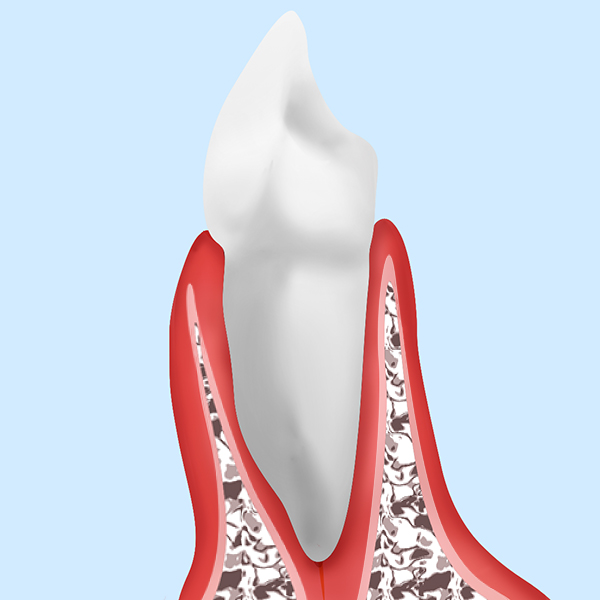

歯周病というのは歯が植わっている土台のアゴの骨を溶かす病気です。

このように歯周病は土台のアゴの骨を溶かしていきます。アゴの骨が溶け続けることにより最終的には歯がグラグラになり抜け落ちていく病気です。

ここで見ていただきたいのは、健康な方と重度歯周病の方の歯茎の高さはあまり変わらないという所です。要するにパッとお口の中だけを見て歯周病かどうかは分かりません。

X線写真の検査をしてはじめてどれだけ骨が溶けて歯周病が進行したかがわかります。